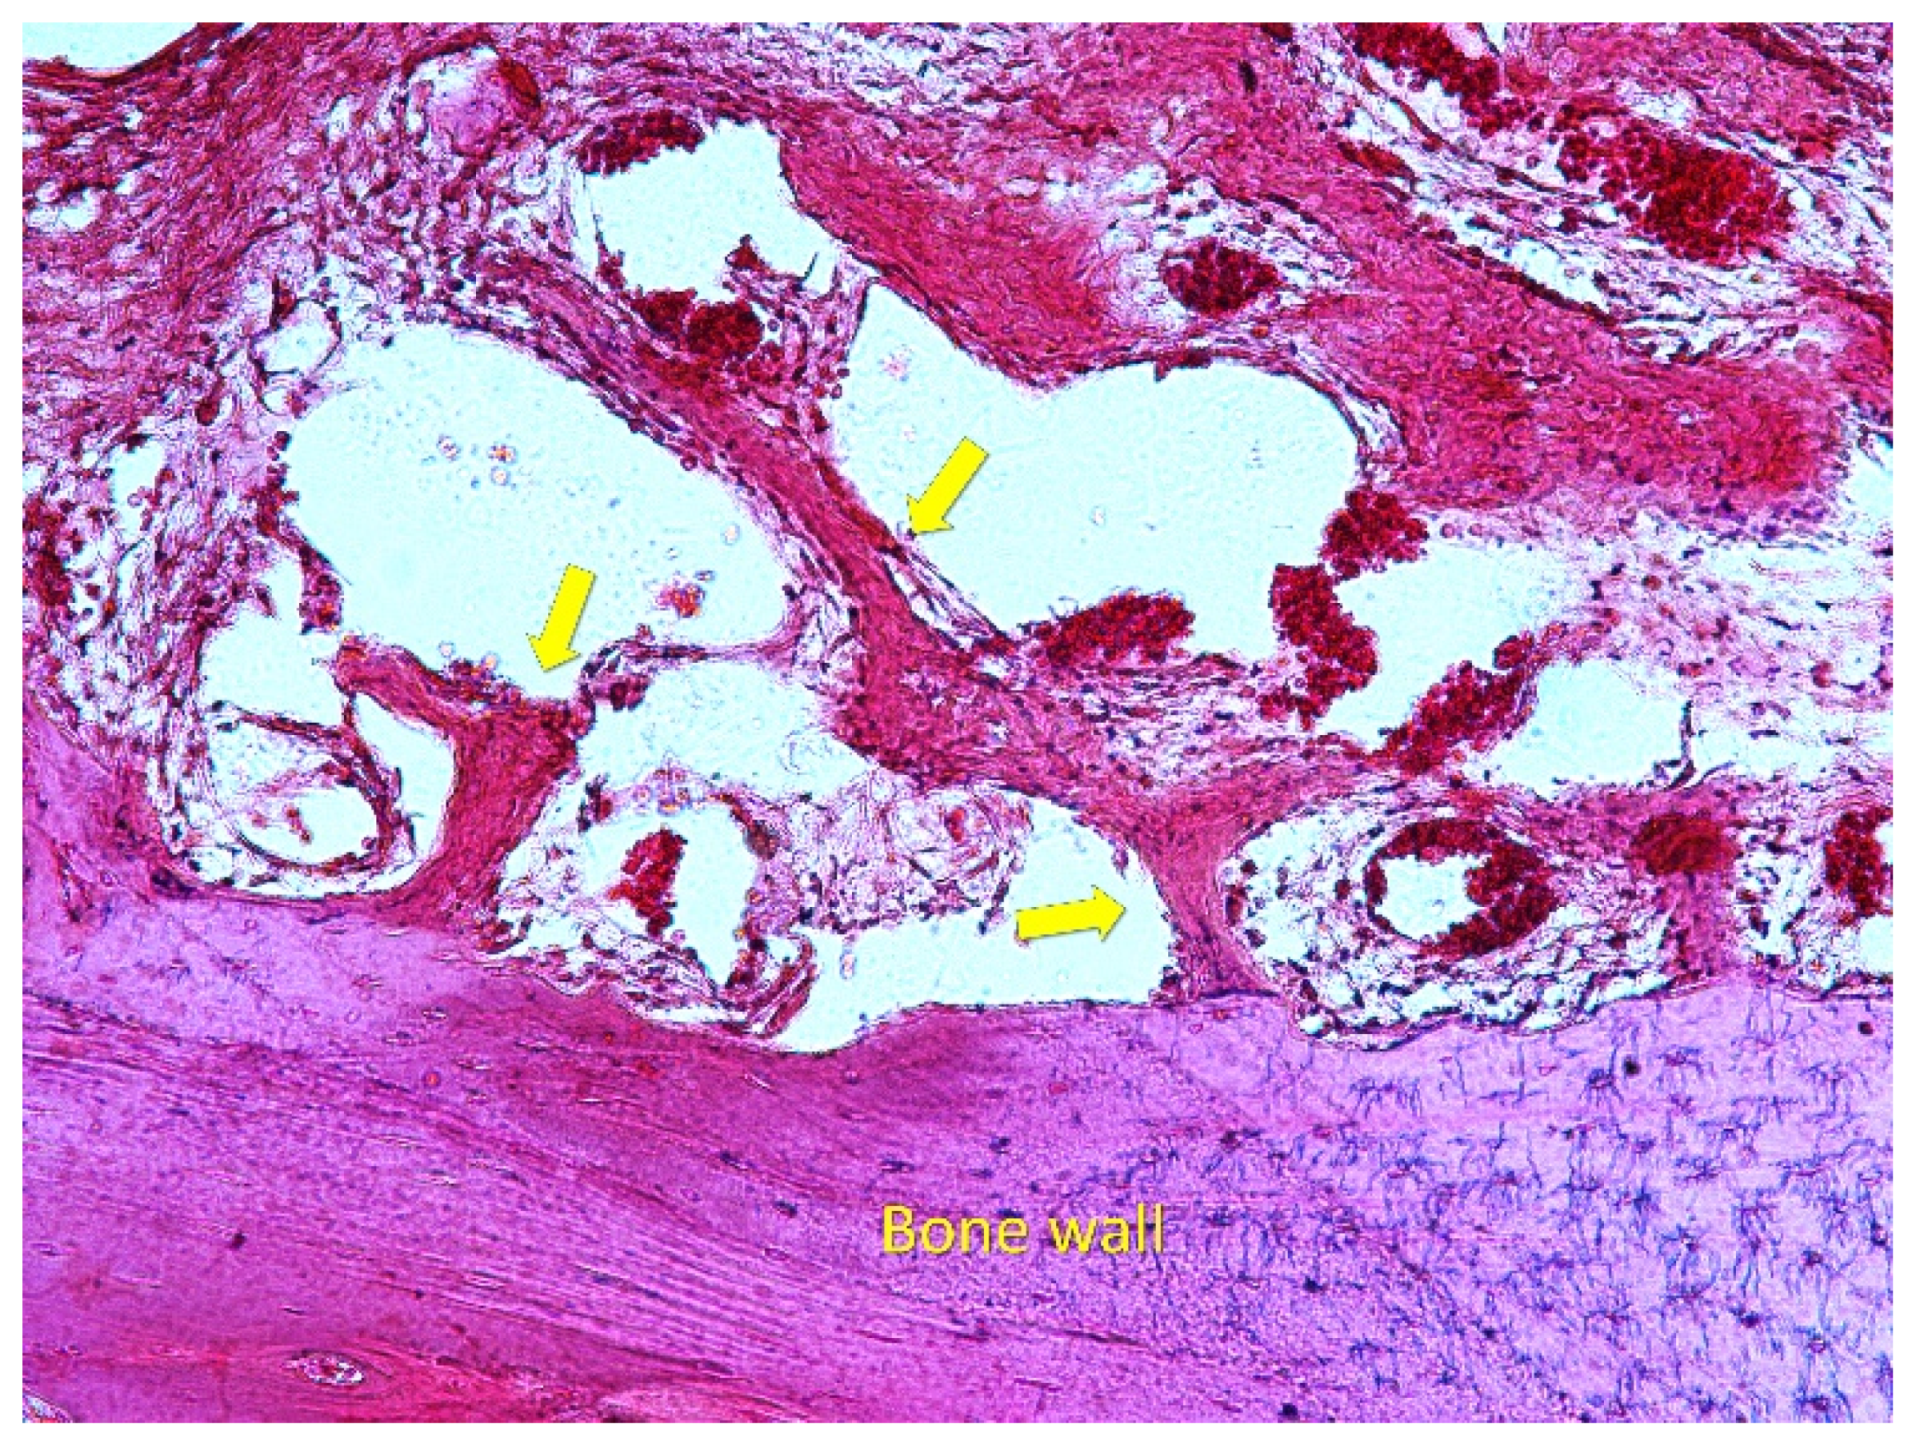

3.2. Osteotomy Region